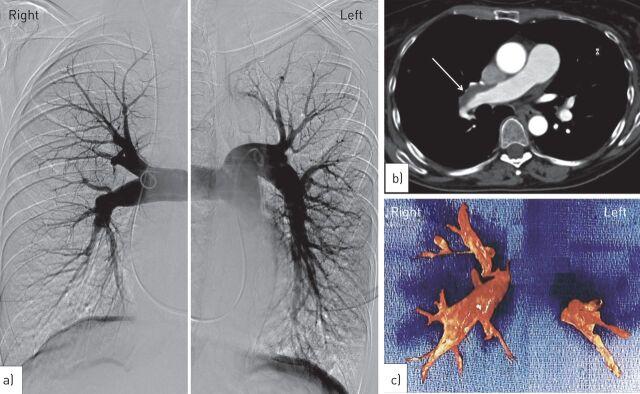

Chronic thromboembolic pulmonary hypertension complicating long-term cyproterone acetate therapy.

Eur Respir Rev. 2014 Jun;23(132):260-3. doi: 10.1183/09059180.00005913.